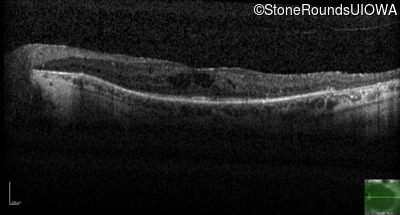

Optical Coherence Tomography - Left - 20/63

Exemplar / OCT Stack

OCT Stack